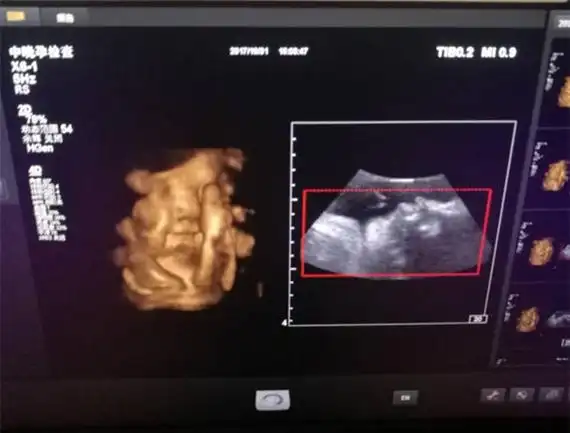

在b超中,怀孕第五个月的男孩和女孩有一个明显的区别:女孩可以看到

nt秒过十二周nt检查看着以为是男宝呢十四周找私人_妈妈网孕育社区

阴囊褶皱